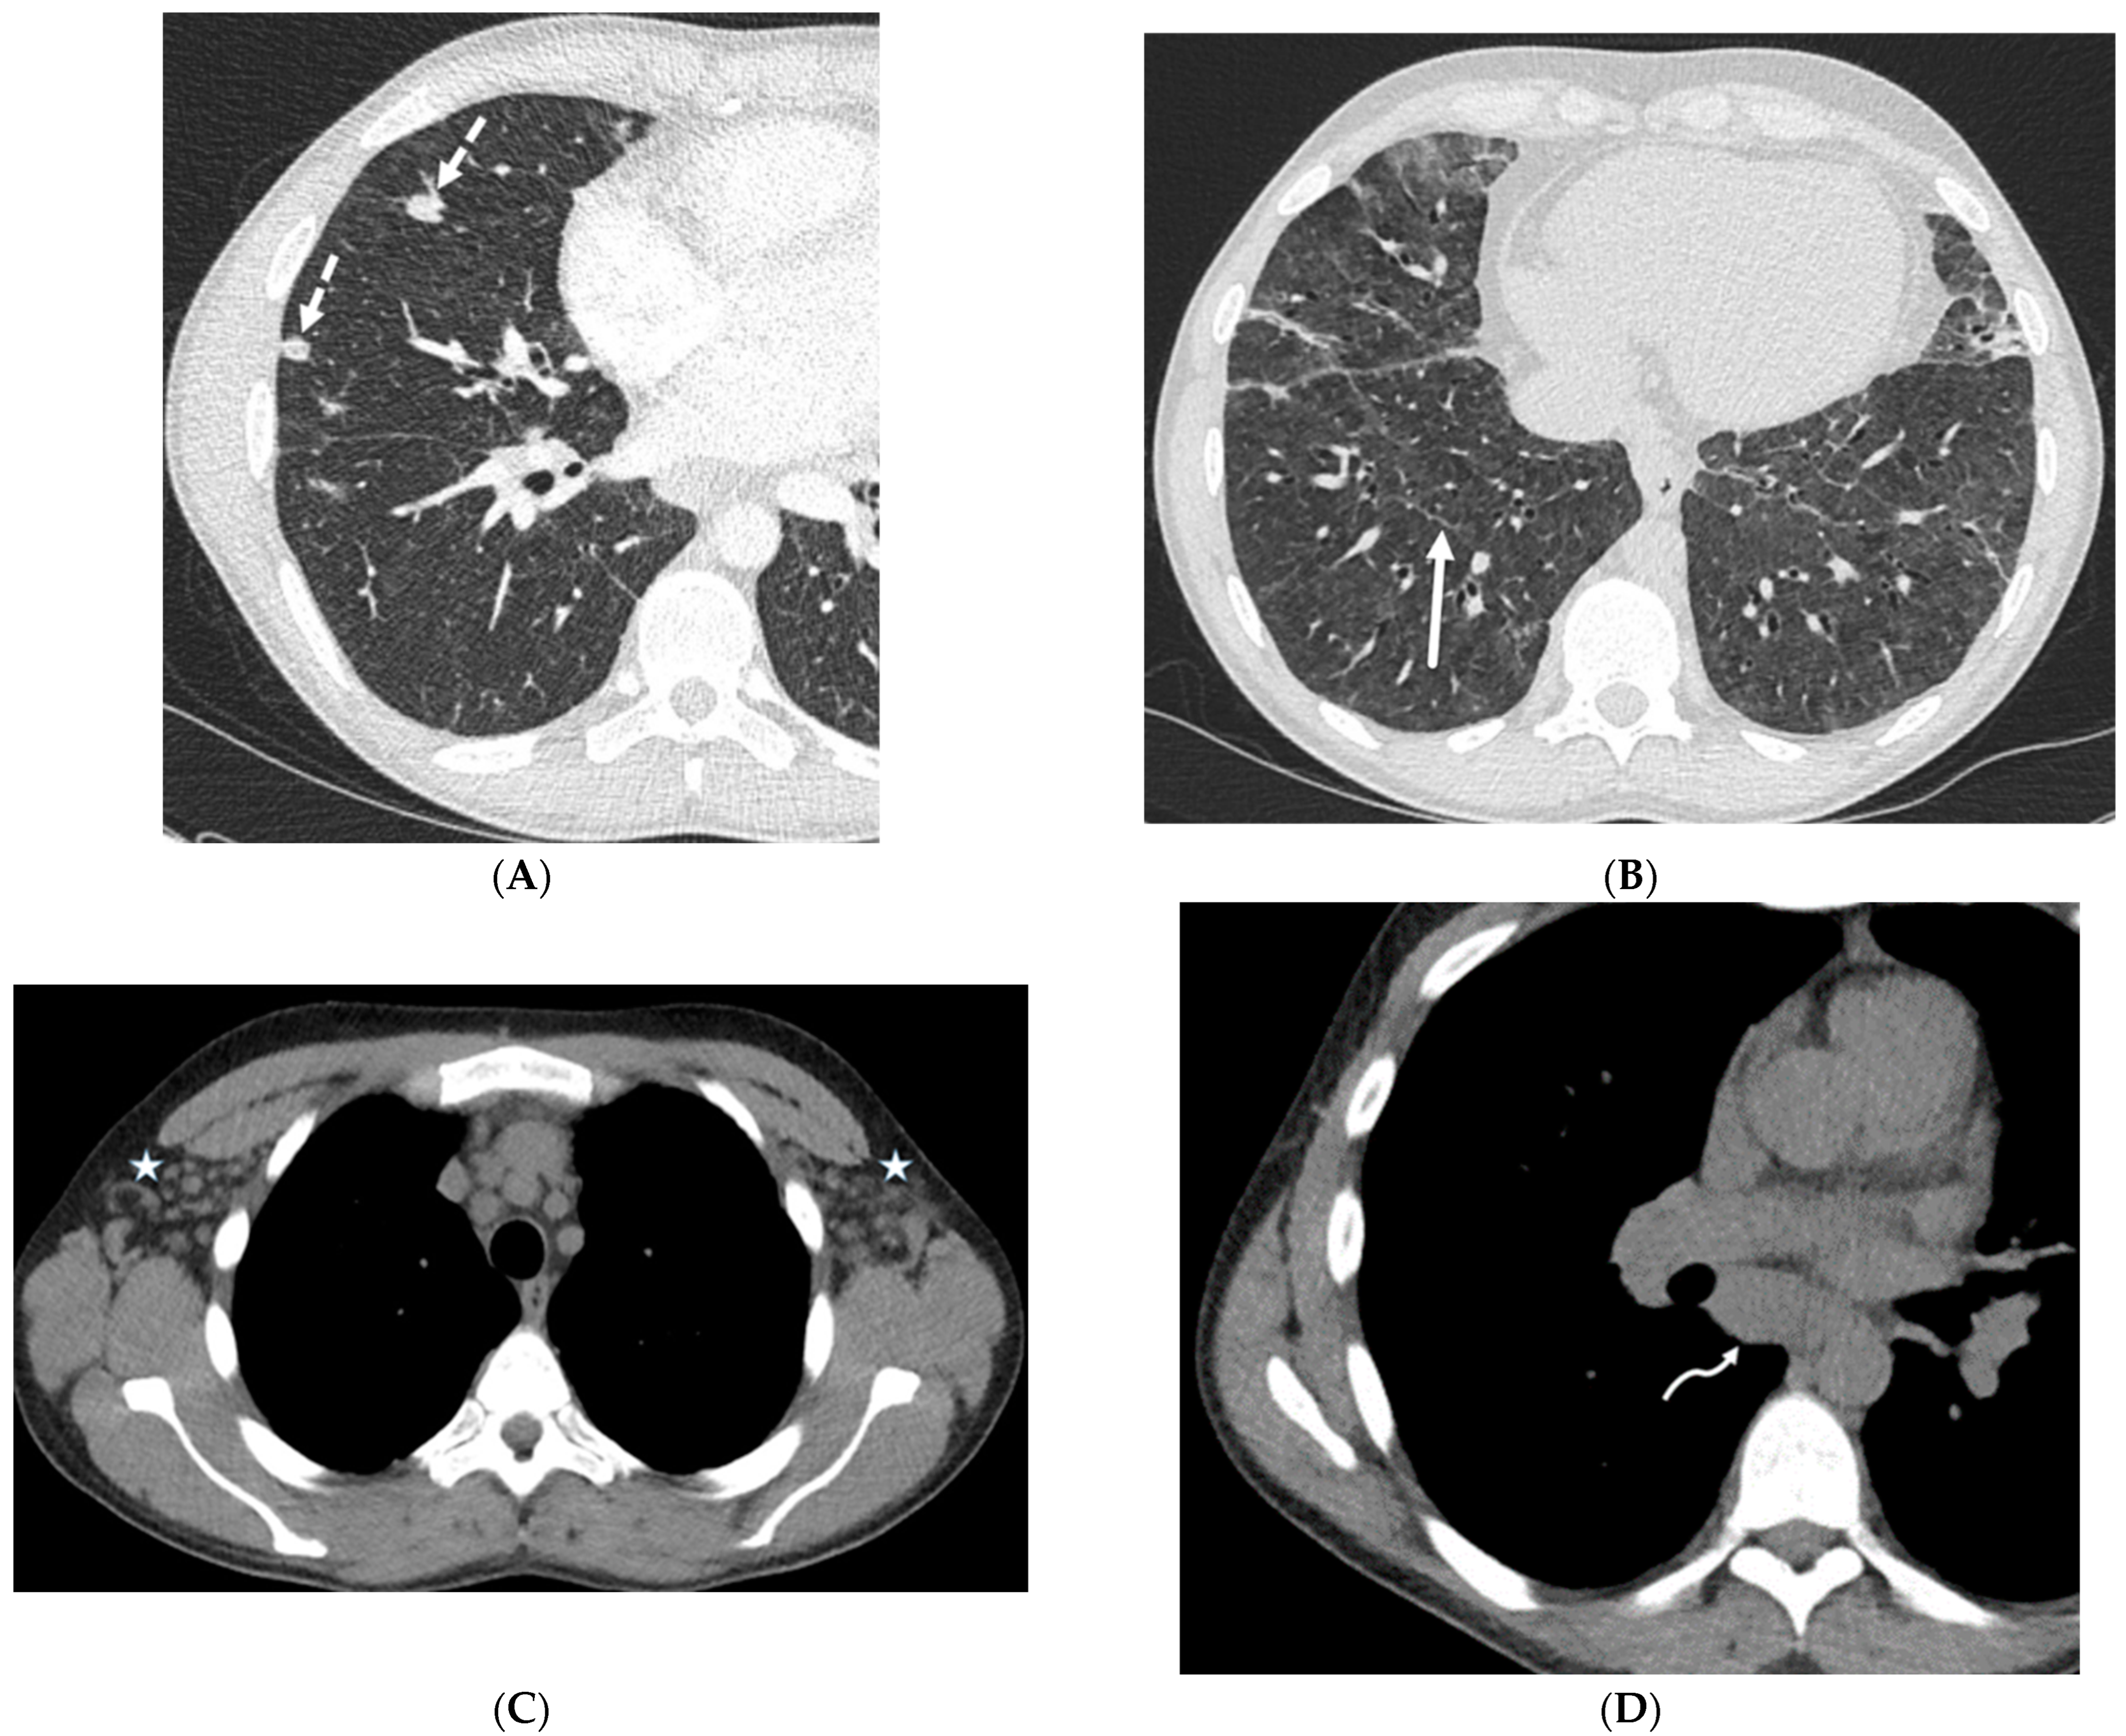

| Silicone embolization | History of illegal cosmetic injection of liquid silicone | Multiple subcutaneous soft tissue attenuation nodules, sometimes with peripheral calcification or surrounding fat stranding |